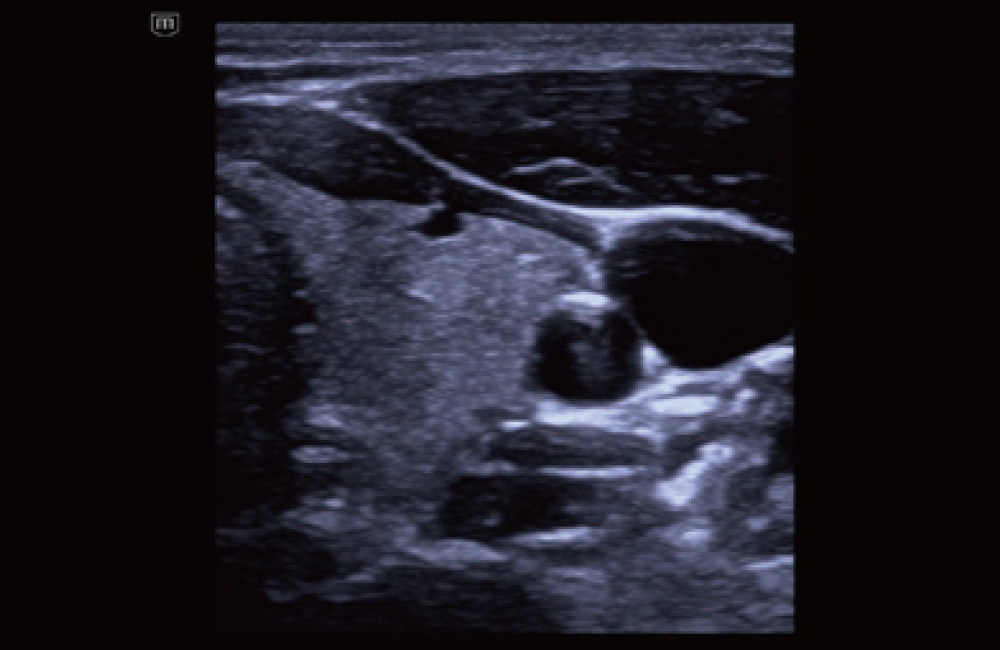

Tireoide com o iTouch+